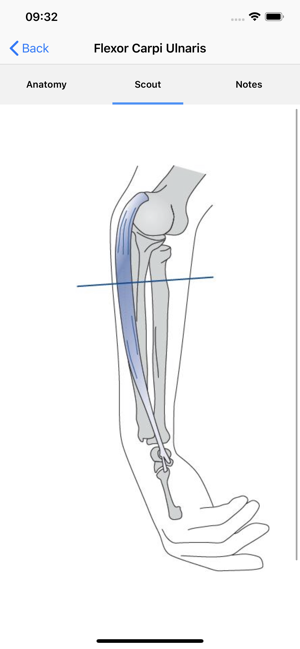

• Improve your skills in identifying muscles and neighbouring structures using ultrasound! • Instructive ultrasound cross-sectional images and videos• Plus: cross sections, scouts and the option for individual annotations• Use it as a Point-of-care APP on your smart phone or as a reference APP for anatomical studies. • Online content for quick reference and updates. Download option for permanent availabilityEntwickler App: Quickbird Studios GmbH, www.quickbirdstudios.comEntwickler Content: Child & Brain GmbH, www.childandbrain.com